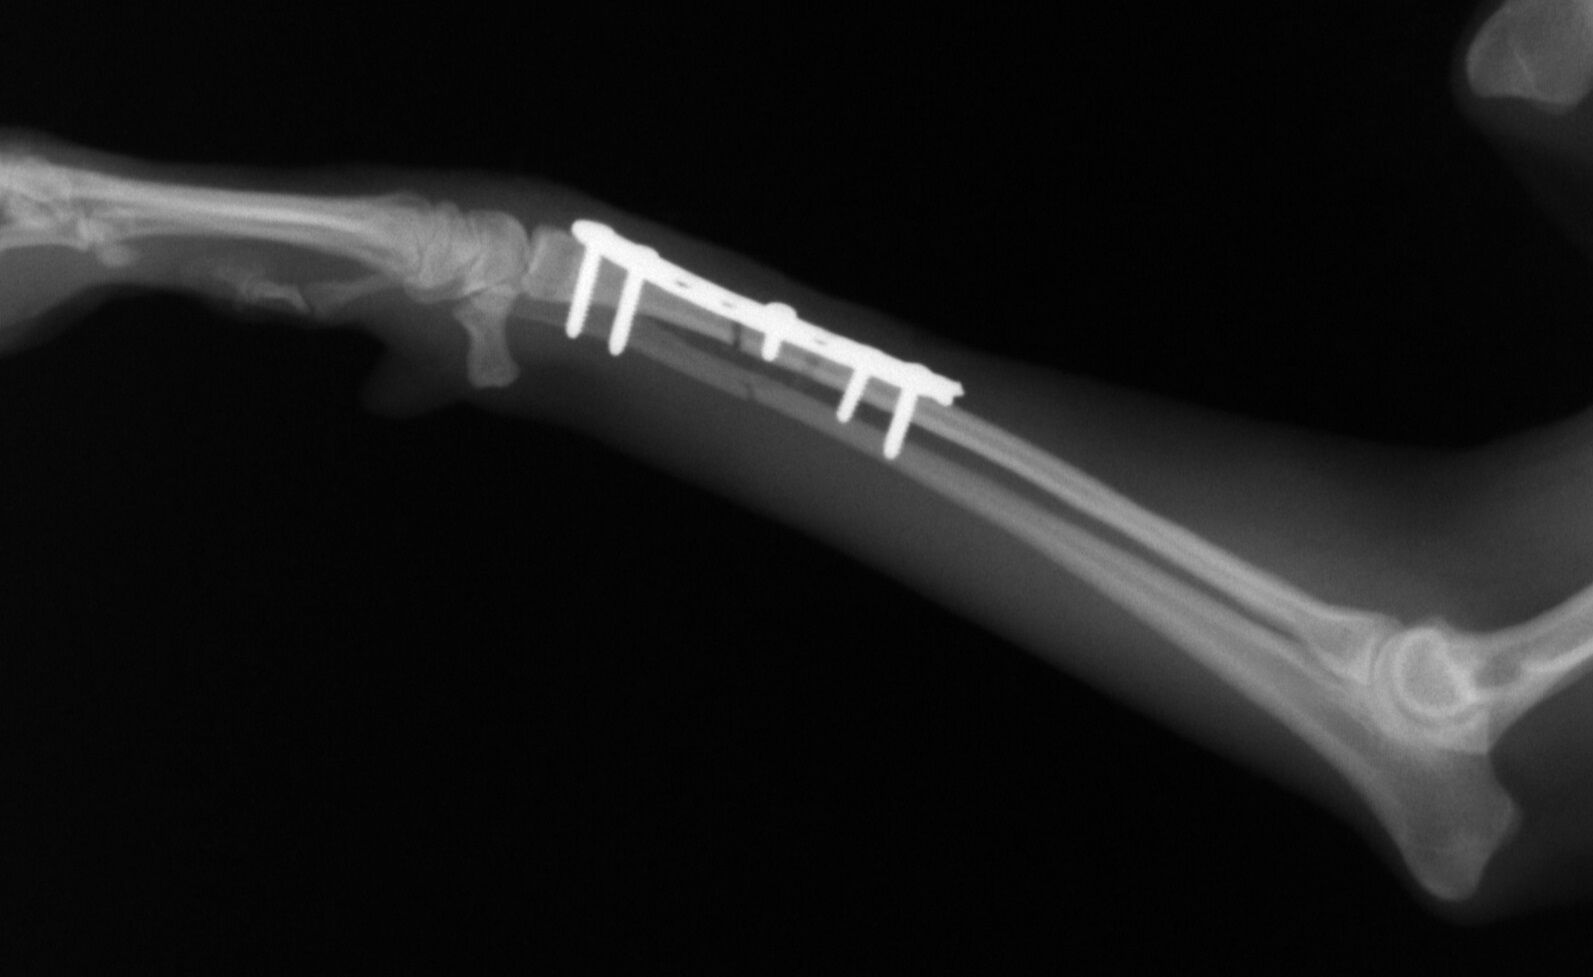

こんばんは、フジタどうぶつ病院です。今日はトイ・プードルの橈尺骨骨折の治療についてご報告させて頂きます。トイ・プードルは脚が長く、骨が細いので非常に骨折が多い犬種です。椅子やソファーから降りた時に折れたり、中には飼い主さんの後ろを歩いていて気づいたら脚を挙げていて病院でレントゲンを撮ったら折れていた、ということもあるようです。今回の症例報告のワンちゃんは椅子から降りた時に折れてしまったようです。下の写真が病院に来院時に撮ったレントゲン写真です。前脚の橈骨と尺骨が折れています。

治療はプレートで固定する方法を行いました。骨折位置が橈骨先端に比較的近い位置だったことと、トイ・プードルは骨の増生が悪いことで有名なので少し気を遣う症例でした。プレートはステンレスプレートを用いました。手術直後が下の写真です。